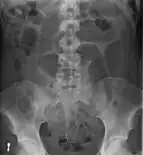

After taking a thorough history, the diagnosis of colonic volvulus is usually easily included in the differential diagnosis. Abdominal plain x-rays are commonly confirmatory for a volvulus, especially if a "bent inner tube" sign or a "coffee bean" sign are seen. These refer to the shape of the air-filled closed loop of colon which forms the volvulus. Should the diagnosis be in doubt, a barium enema may be used to demonstrate a "bird's beak" at the point where the segment of proximal bowel and distal bowel rotate to form the volvulus.

This area shows an acute and sharp tapering and looks like a bird's beak. If a perforation is suspected, barium should not be used due to its potentially lethal effects when distributed throughout the free intraperitoneal cavity. Gastrografin, which is safer, can be substituted for barium.